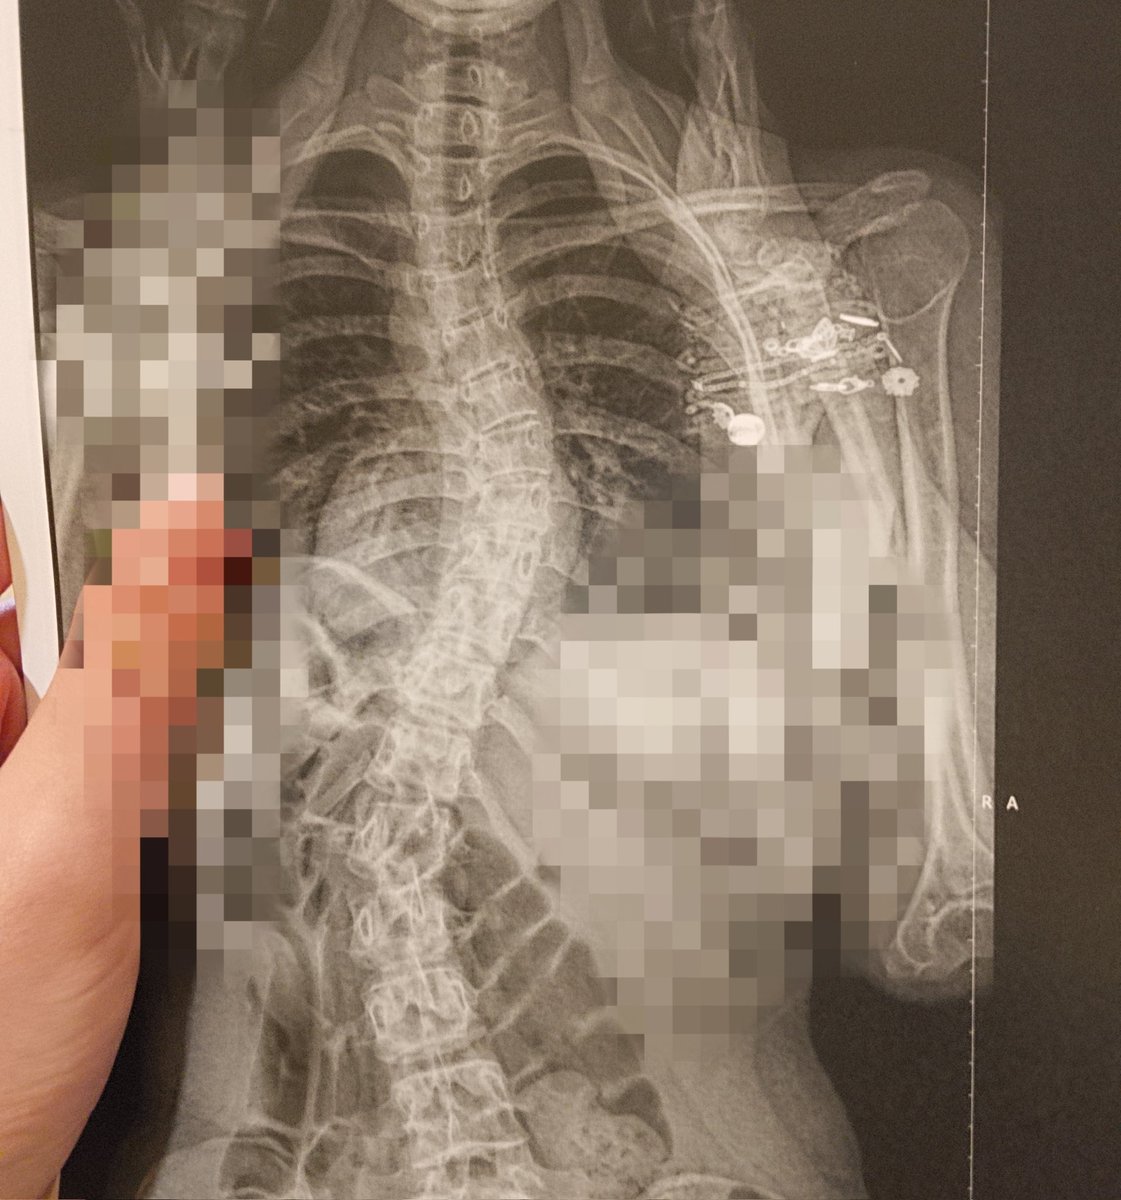

Gemma🕊️@NatsBrokenSpine

Hi

English